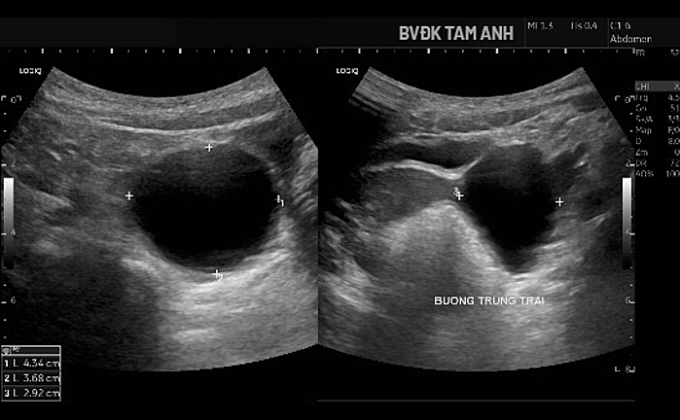

Hình siêu âm cho thấy nang buồng trứng phì đại. Ảnh: Bệnh viện Đa khoa Tâm Anh

Ngoài ngực phát triển,bé Huyền chưa xuất hiện dấu hiệu dậy thì khác. ThS.BS Đỗ Tiến Sơn,khoa Nhi,Bệnh viện Đa khoa Tâm Anh Hà Nội,ghi nhận tuyến vú của trẻ đã phát triển ở giai đoạn Tanner B3 - giai đoạn bắt đầu xuất hiện mô tuyến vú nhanh và rõ. Buồng trứng trái có nang lớn kích thước khoảng 43x37x29 mm,thành mỏng,chứa dịch trong,bên trong có nang nhỏ. Tổn thương được xếp loại ORADS 2,nguy cơ ác tính thấp. Chụp MRI xác định nang buồng trứng trái lành tính. Kết quả X-quang đánh giá tuổi xương chưa tăng,hiện phù hợp với tuổi thực của bé.